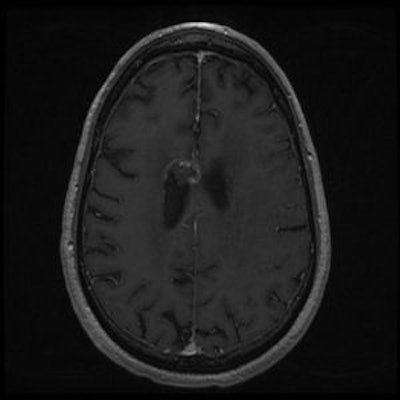

| A 43-year-old man with oligodendroglioma. Above, axial T1 + contrast brain MRI before Gamma Knife treatment. Below, axial T1 + contrast brain MRI two years after Gamma Knife treatment. Images courtesy of Dr. Allison Quick. |

For all patients, a thin-cut (1.3- to 1.5-mm slices) stereotactic MRI exam was performed with axial T1 and T2 images used for planning. Gross tumor volume was contoured, and the single dose prescribed ranged from 1,000 cGy to 2,000 cGy prescribed to the 50% isodose line. The average dose was 1,611 cGy, and the average target volume was 6.34 cm³, with a range of 60.4 mm³ to 22.4 cm³.